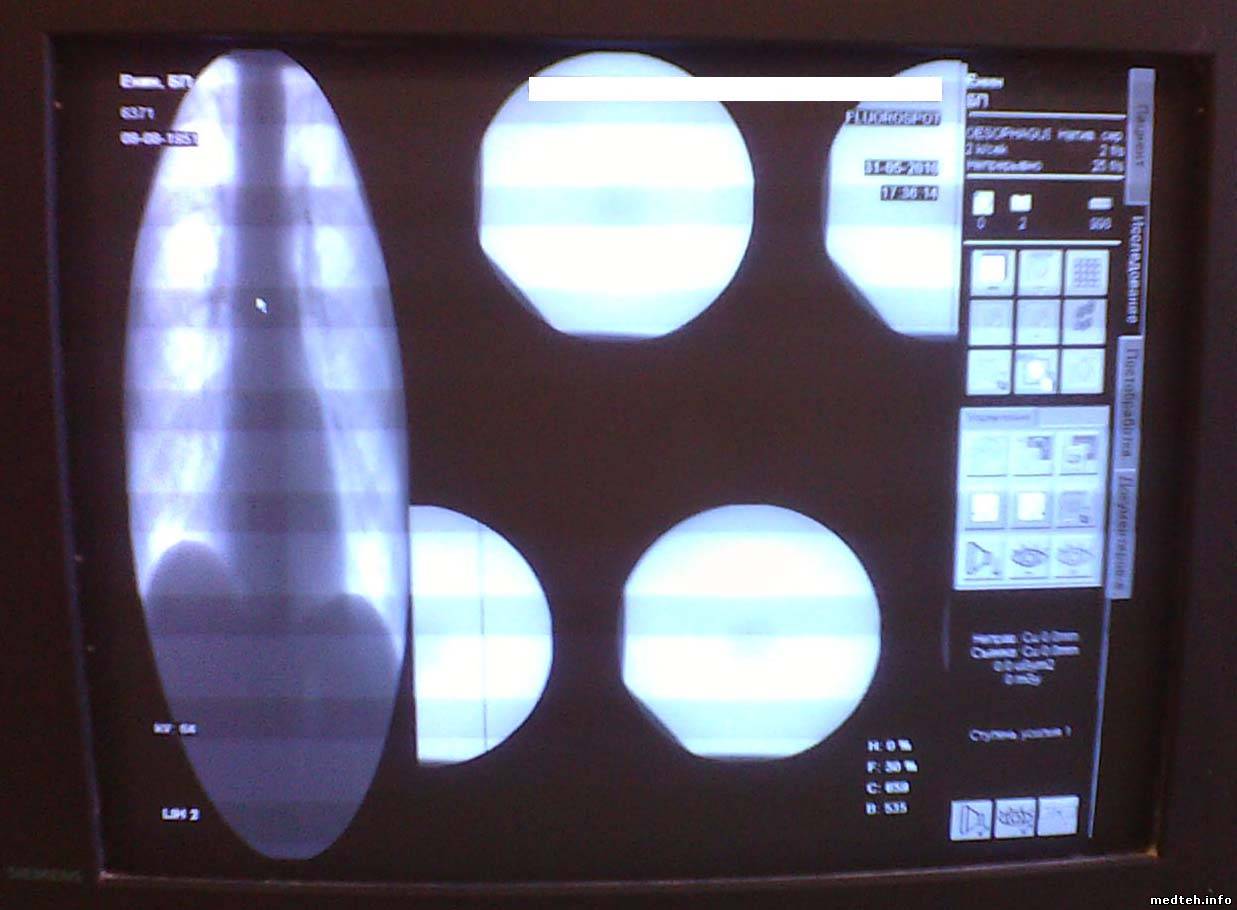

| Форум медтехников Медицинское оборудование (тех. разделы) Рентгеновское оборудование. Проблема изображения на Siemens Iconos R200 |

| Проблема изображения на Siemens Iconos R200 | |||||||||